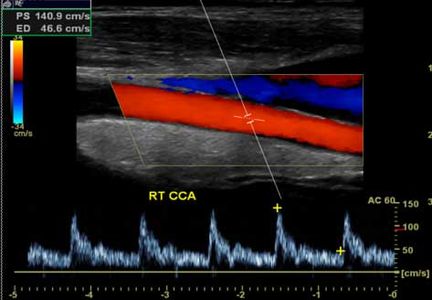

A carotid ultrasound is a non-invasive test that uses ultrasound to produce images of the carotid artery in the neck which measures the blood flow to the brain and can determine blockages to reduce risk of stroke